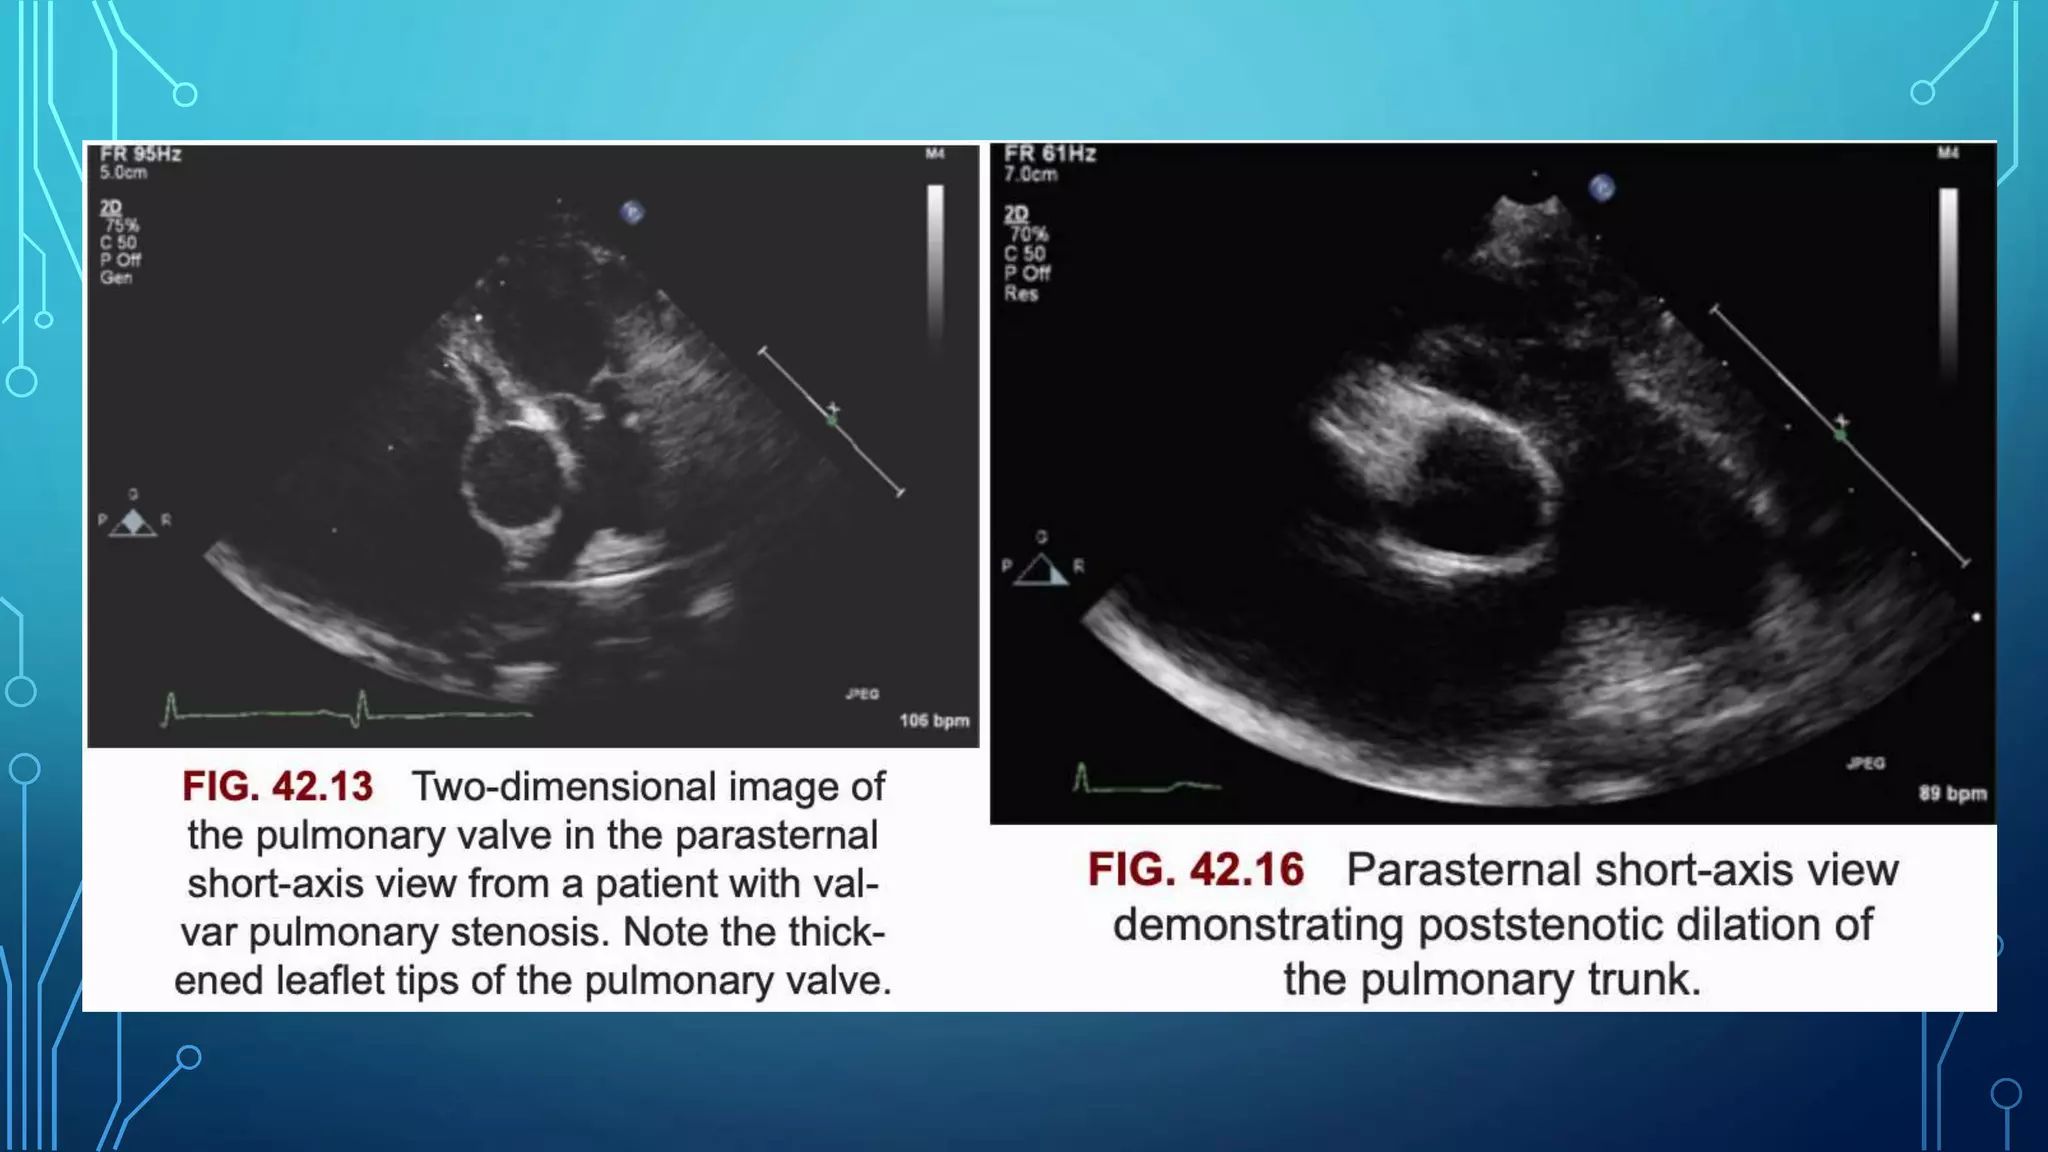

• Two-dimensional echocardiographic precordial short-axis and

subcostal views are most useful in the evaluation of the

pulmonary valve leaflets

• Thickening and doming of the pulmonary valve leaflets can

often be visualized

• Markedly thickened, nodular, and immobile pulmonary valve

leaflets, suggestive of dysplastic pulmonary valves

• The pulmonary valve annulus can also be visualized and

measured

• Such measurements are also useful in the selection of balloon

diameter for balloon valvuloplasty